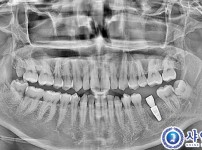

147

뼈이식임플란트 - 스트라우만록솔리드